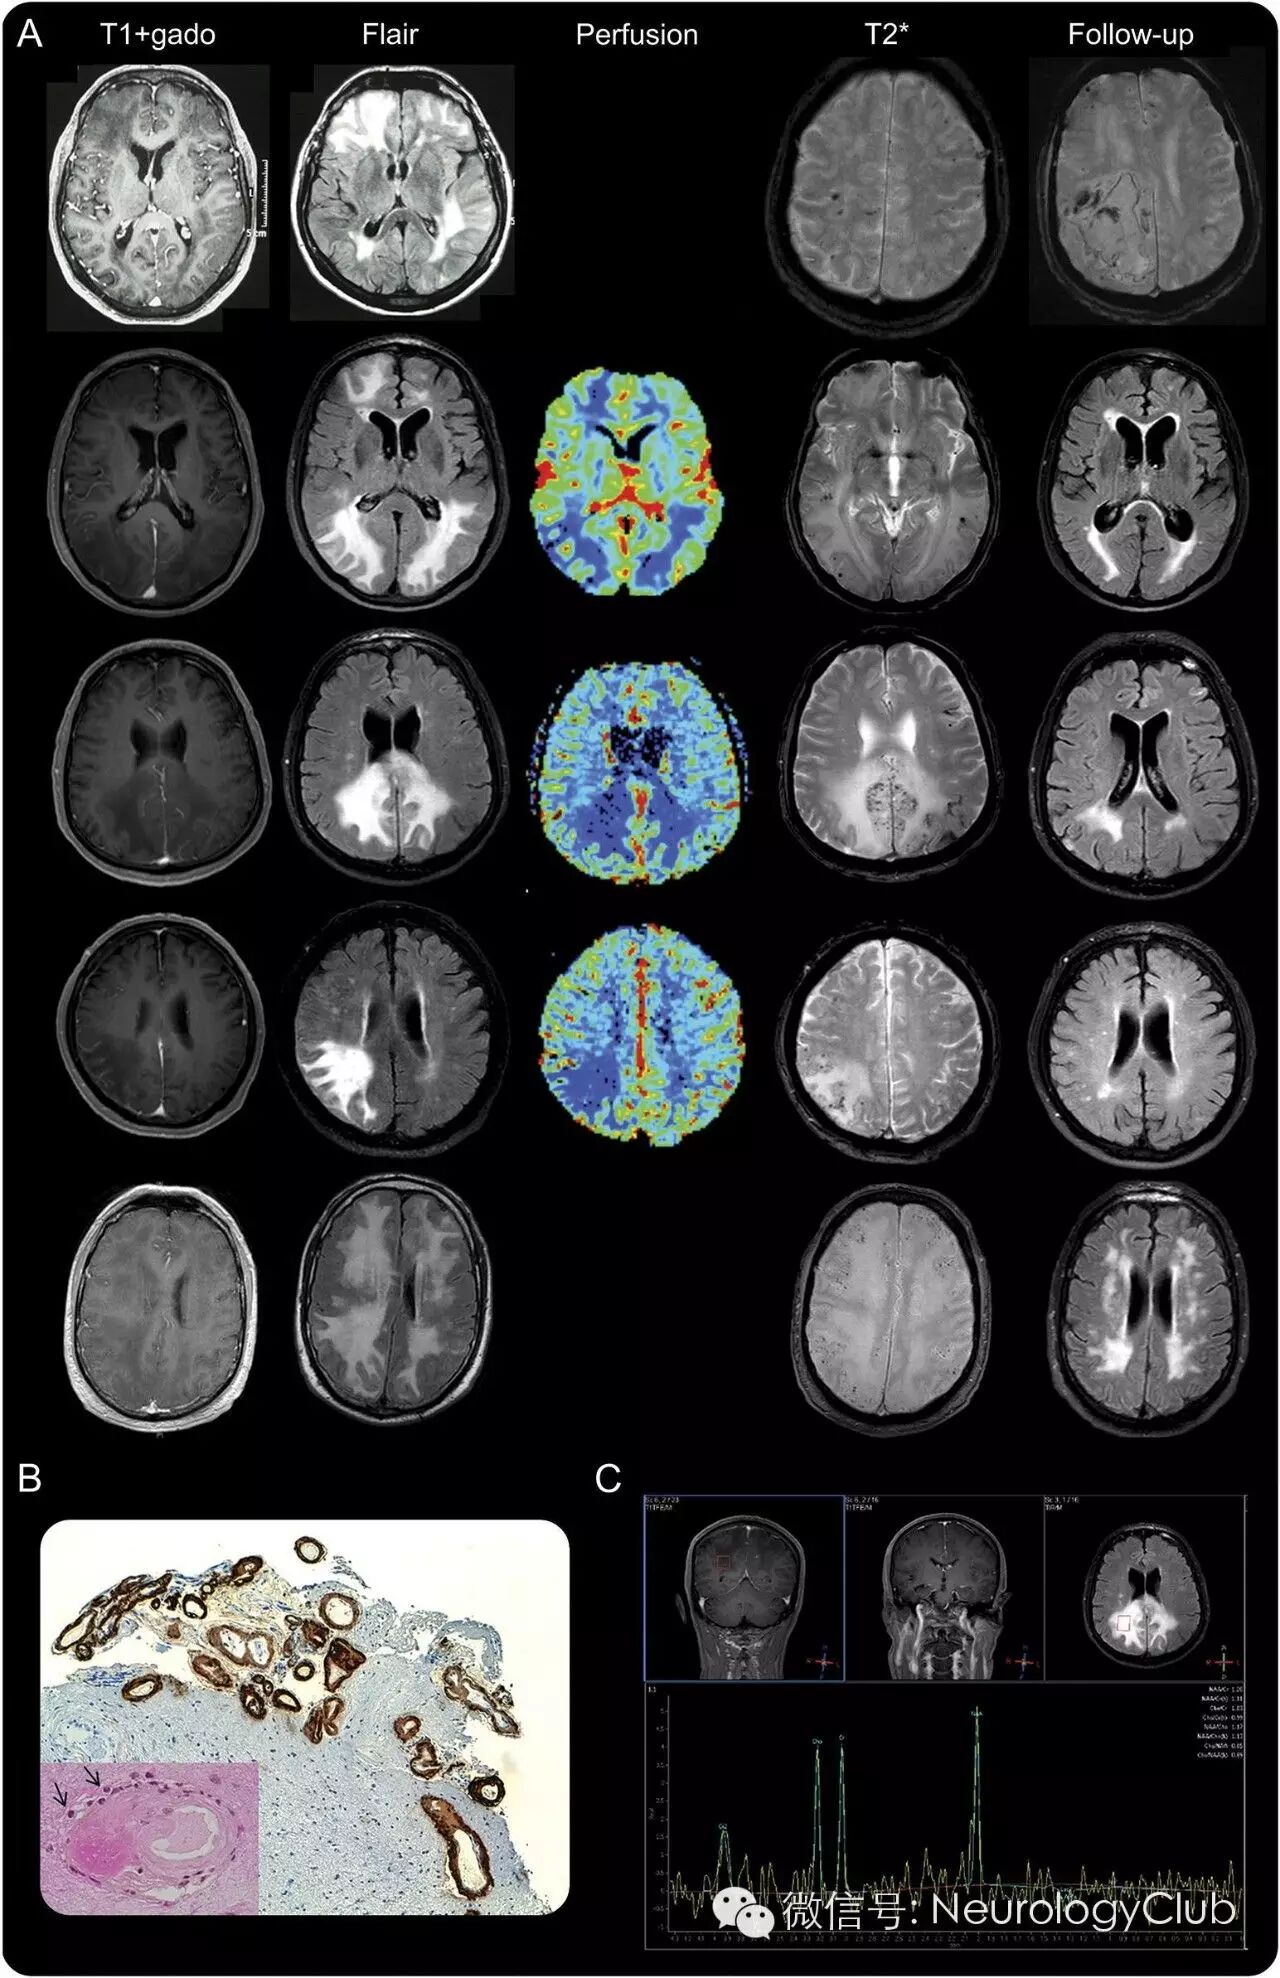

(假瘤样表现的CAA-I患者的影像学和病理资料。A:5例患者起初和随访时的MRI发现;T1增强和FLAIR上可见幕上白质病变伴占位效应,无脑实质强化;伴有T2*WI上多发皮质微出血;MRI灌注上相对脑血容量明显下降;随访时,第1例患者T2*WI上可见急性脑叶血肿,2-5例患者FLAIR上可见高信号病灶明显减退;B:第1例患者脑组织Aβ免疫组化提示柔脑膜和皮质血管内淀粉样蛋白沉积[×100];左下角图可见因淀粉样蛋白沉积而明显增厚的血管周围轻度炎性浸润[箭,×400];C:第3例患者质子磁共振波谱无异常发现